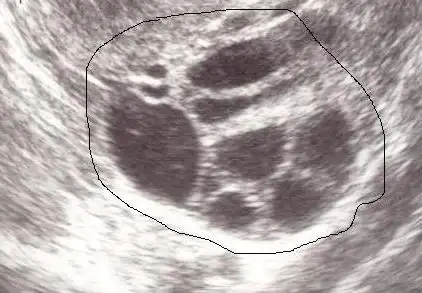

bu resmi gorsem pkos derdim demekki cesitleride varmis rabbim emeklerimizi bosa cikarmasin canim sen pkoslar icin yag setini duydunmu ben yarin ins. baslayacagimEki Görüntüle 2169726 Eki Görüntüle 2169727

multifolliküler over

multifollilülerde kilo yok, tüylenme vb yok. adet düzensizliği olabiliyor. hafif pco over benzeri bir durum.